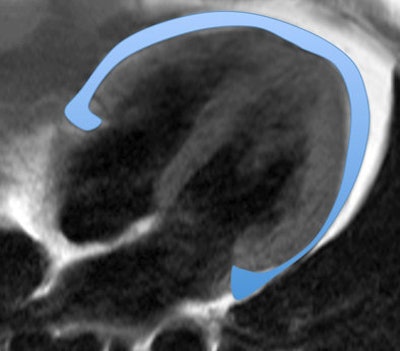

ECG-gated T1-weighted dark blood turbo spin-echo sequences were acquired in short- and long-axis views on a 1.5-tesla system (Siemens Healthcare). The study team quantified epicardial and paracardial adipose tissue between the atrioventricular plane and the apex using QMass 71 software (Medis).